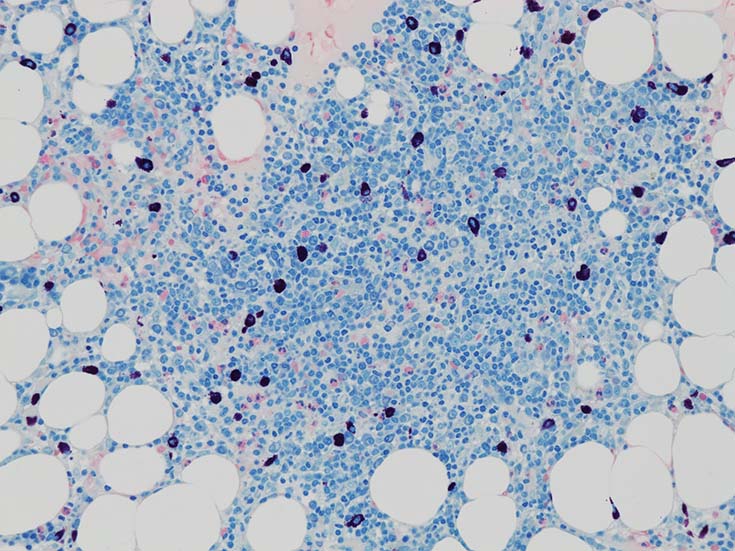

Bone marrow clot sectionでは, nodularな病変形成が認められる. HEでは不明瞭であるが, Naphtol-ASD-CAE-Giemas染色では mast cellの顕著な増加が明瞭に認識される.

mast cellsは周辺部に出現することが多いようである.多発性骨髄腫の結節にはmast cell増加を認めることは経験上ない.